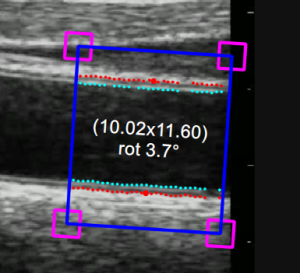

B-mode ROI

T he B-mode Region of Interest (ROI) is the portion of the image where both the diameter and the IMT are calculated. The points of the Lumen-Intima interface and the Media-Adventitia interface are displayed within the ROI in cyan and red color respectively. The ROI can be moved, resized, and/or rotated. Each time you change the position, size and/or inclination of the ROI, the analysis is re-initialized.

• Click inside the video window and drag until the ROI is complete (the size of the ROI is shown in the Setup panel and graphically within the ROI).